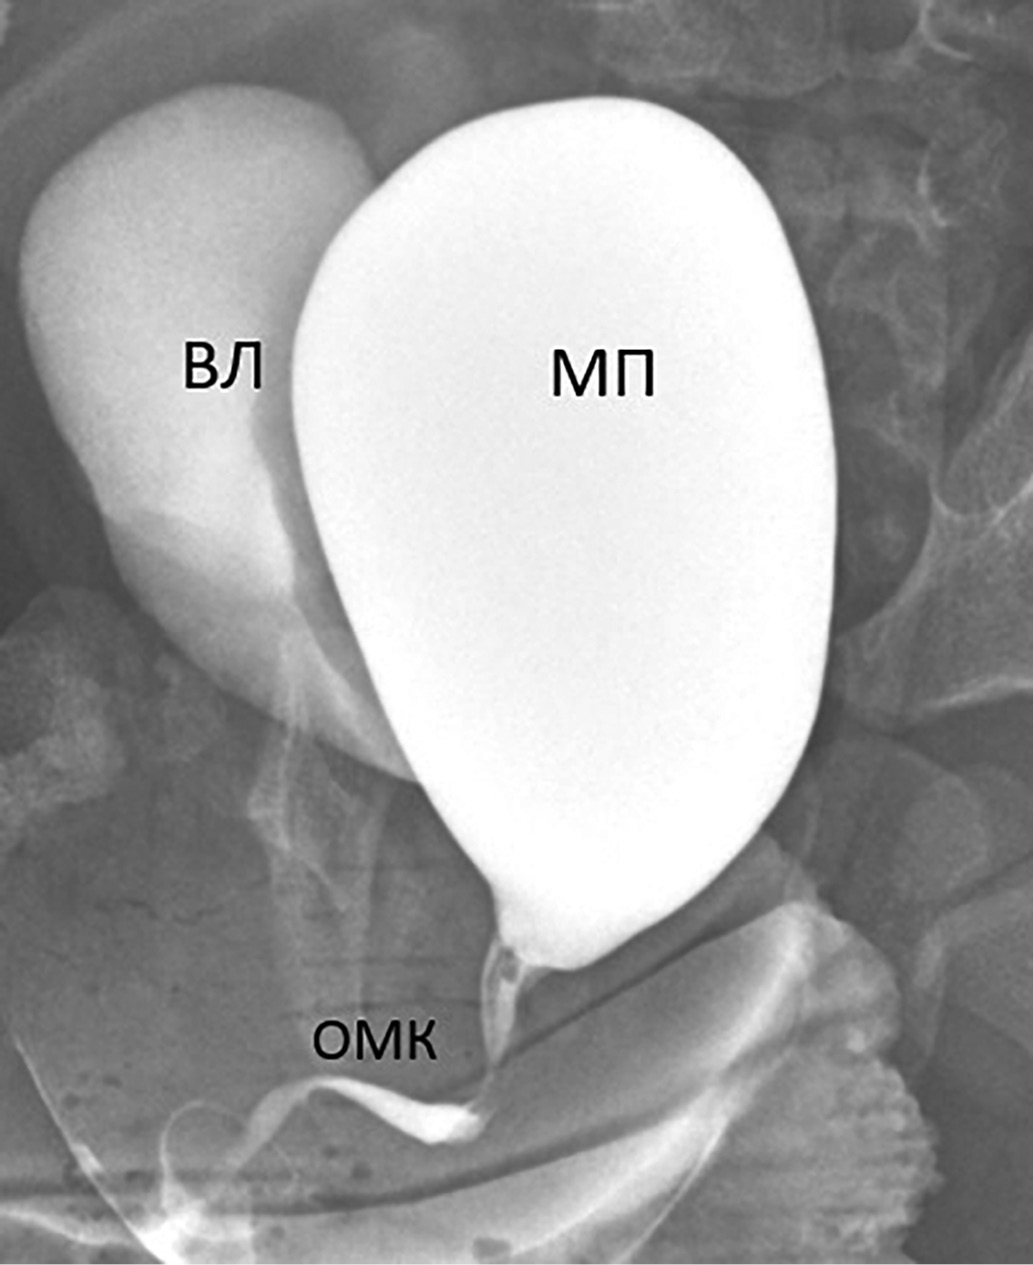

Рисунок 1. Микционная цистоуретрограмма у девочки раннего возраста с сольтеряющей формой врожденной дисфункции коры надпочечников. Определяются уретро-вагинальный рефлюкс (при мочеиспускании влагалище (ВЛ) заполняется контрастным веществом) и длинный, извитой, сформированный по мужскому типу общий мочеполовой канал (ОМК). МП — мочевой пузырь.

1. Рисунок 1. Микционная цистоуретрограмма у девочки раннего возраста с сольтеряющей формой врожденной дисфункции коры надпочечников. Определяются уретро-вагинальный рефлюкс (при мочеиспускании влагалище (ВЛ) заполняется контрастным веществом) и длинный, извитой, сформированный по мужскому типу общий мочеполовой канал (ОМК). МП — мочевой пузырь. | |